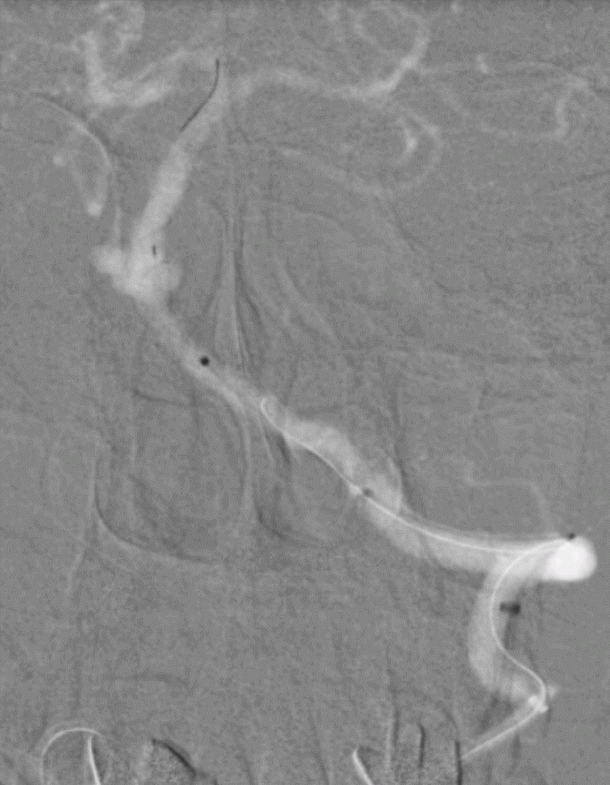

成功穿刺左侧远桡动脉后,置入6.5F薄壁桡动脉鞘,V18+Fastrack微导管支撑下,DA顺利进入L-V1段。

2

0.014 Synchro微导丝携Fastrack微导管至L-P1,引入4mm*20mm Tubridge血流导向密网支架。

3

Tubridge血流导向密网支架释放,回拉定位,逐步推挤释放支架。

4

释放完毕后跟进支架导管,回收输送导丝,微导丝成袢行支架内按摩。